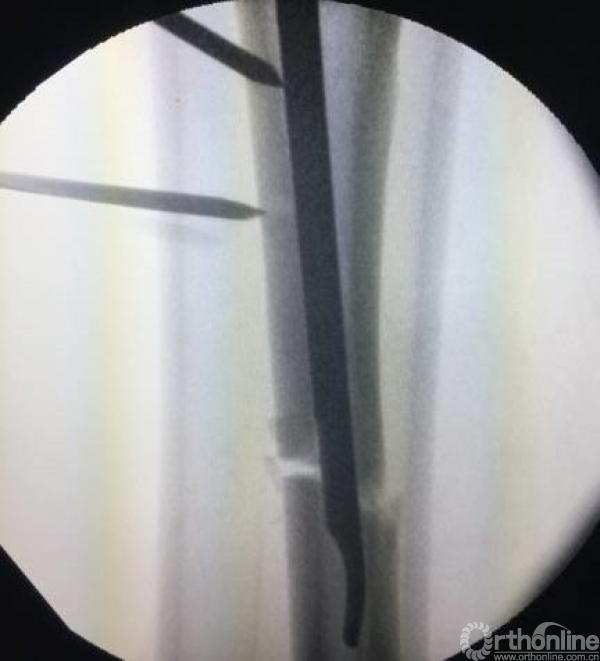

当骨折线经进钉点时,可先行头颈克氏针固定。

对于多端的骨折,需要善于应用阻挡钉技术。

摇杆技术+金手指技术进行复位。

远端时,防止后倒和摆动增加阻挡钉。